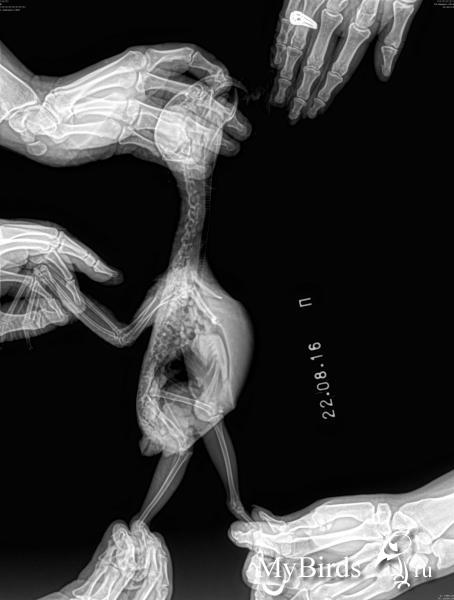

В январе начала обгрызать перья на крыле - буквально брала крыло в лапу и грызла, самец начал отгонять от кормушек, отсадили в отдельную клетку, через пару дней она вообще перестала есть. Когда взвесили, она весила 350 грамм, т.е. проблемы с едой были уже давно, но я недосмотрела. Начались проблемы с пометом. Давали энтерол, карсил, линекс, метионин, мезим, но-шпу, йогурт - уже не помню, что с чем и в какой дозировке. Пищеварение наладили. Птица была куплена за год до этого, у нее изначально слезились глаза, но анализ на микоплазмоз был отрицательный (сейчас я понимаю, что результат был неверный, или написан от фонаря). В начале февраля сдали опять в Бальде анализ на микоплазмоз, бакпосев, копрограмму, смыв на грибок из зева и глаза. Микоплазмоз был отрицательный, НО смутило то, что при явных нарушениях пищеварения копрограмма была идельной. В общем, этим анализам не верю. Еще появились проблемы с лапой, при ходьбе по ровной поверхности она подгибалась вовнутрь, если дать в лапу палец, то она его не отпускала. Врач предположил, что микоплазмоз все-таки есть и мы начали давать сумамед. Врач предложил два варианта лечения: сумамед в течение месяца или 2 недели сумамед + 2 недели макропен. Второй вариант он предложил как менее гепатотоксичный, и мы на него согласились. На сумамеде вначале было обострение в виде насморка (даже у второго попугая, у которого симптомов до этого никаких не было) а потом все наладилось, прошло слезотечение, а когда начали макропен - все началось снова. Кроме антибиотиков давали витамины В1, В6, В12, линекс, пимафуцин. Сустав на крыле воспалялся, под кожей как бы появлялась жидкость. Сдали анализы в государственной лаборатории, которая обслуживает птицефабрики. У Маши обнаружена микоплазма, а у второго попугая - микоплазма и орнитоз (у него симптомов никаких не было). Потом был доксициклин 6 недель. Он не помог - слезотечение сохранялось, сустав на крыле время от времени воспалялся. Врач предложил выждать как можно дольше и опять начать сумамед. В середине августа она опять начала грызть крыло, воспалился сустав, и 16 августа начали опять сумамед. Три дня назад появились небольшие хрипы при дыхании, а со вчерашнего дня дыхание очень затруднено. Колю дексаметазон по 0,04 - 4 раза в день. Анибиотик не отменяла. Сегодня поехали не рентген. Снимки прикреплены. Все это время, с февраля, птица практически не ест сама - у нее стоит в корме Престиж для жако, из которого она иногда выбирает семечки. Вес за первый месяц болезни набрали с 350 до 400 грамм, на этом набор остановился.

Это аспергиллез? Если да, то чем лечить и что делать с антибиотиком? Продолжать? Как лечить и аспергиллез, и микоплазмоз? Деньги на Вифенд найду.

По рентгену невозможно поставить диагноз аспергиллез.

Рентген который Вы прикрепили очень жесткий, в боковой проекции область грудных воздухоносных мешков нормально визуализируется.

У птицы нет одного крыла? или это такой снимок?